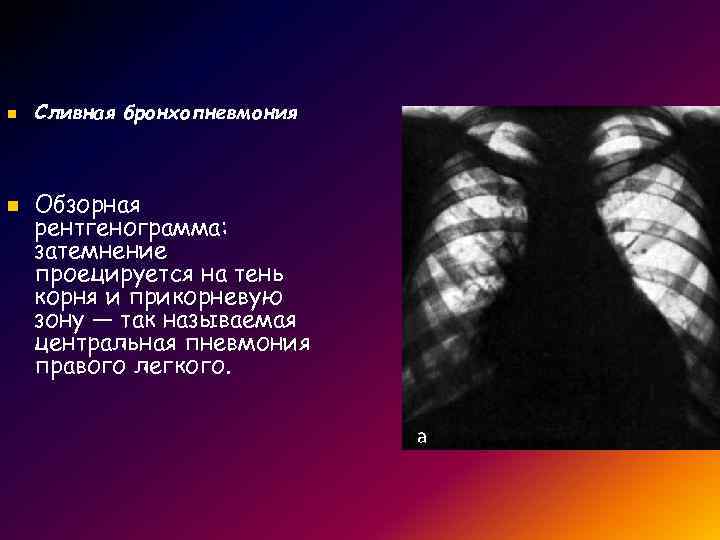

Рентгенодиагностика бронхопневмонии: Советы и примеры

Раздел: Альбом открытий